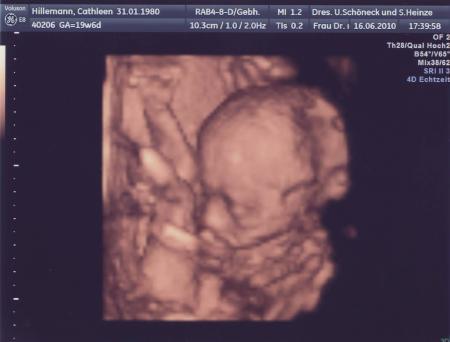

Na dann herzlichen Glückwunsch zur Tochter . Hatte am 23.06. auch FD und wir bekommen nach unserer Großen (4) auch wieder nen Mädel und freuen uns sehr darüber. Hier mal ein Photo unseres Krümels. Cathleen

Bild zu